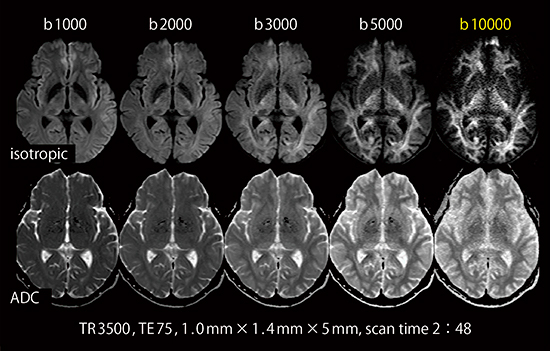

Gmaxが高いとさまざまな利点がある。最も恩恵を受けるのは拡散強調画像で,従来装置に比べて大幅にTE短縮ができるため,SNRの高い画像が得られる。Gmax70mT/mの場合,b値1000s/mm2,128×128マトリックスにおいては最短TE29msであり,b値10000s/mm2といったhigh b値の撮像でもSNRが担保できる(図3)。

図3 High b value DWI